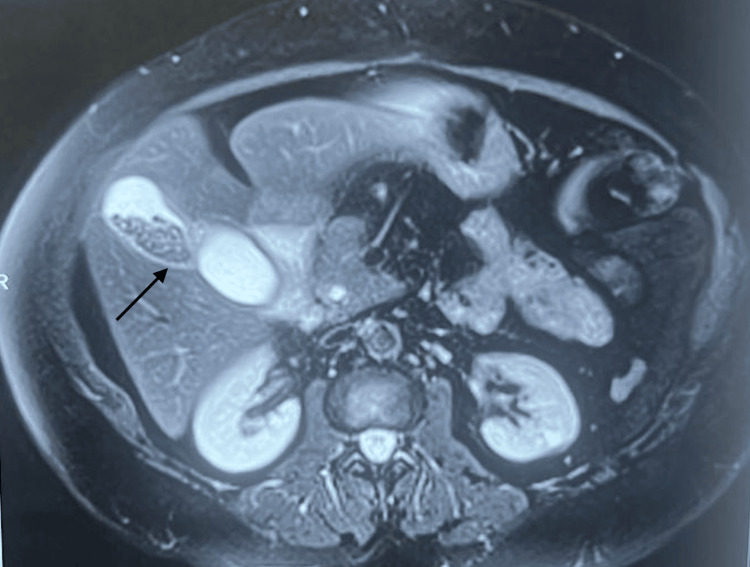

Magnetic resonance cholangiopancreatography (MRCP) revealed a bi-lobed duplication of the gallbladder, with one lobe exhibiting signs of calculous cholecystitis. Intrahepatic and extrahepatic biliary ducts were mildly dilated (Figure 2).

The common bile duct (CBD) measured 8 mm in diameter and displayed a 3.9 x 2.7 mm filling defect, suggestive of choledocholithiasis. Notably, MRCP also identified a 4.3 x 2.1 cm duodenal diverticulum (Figure 3).